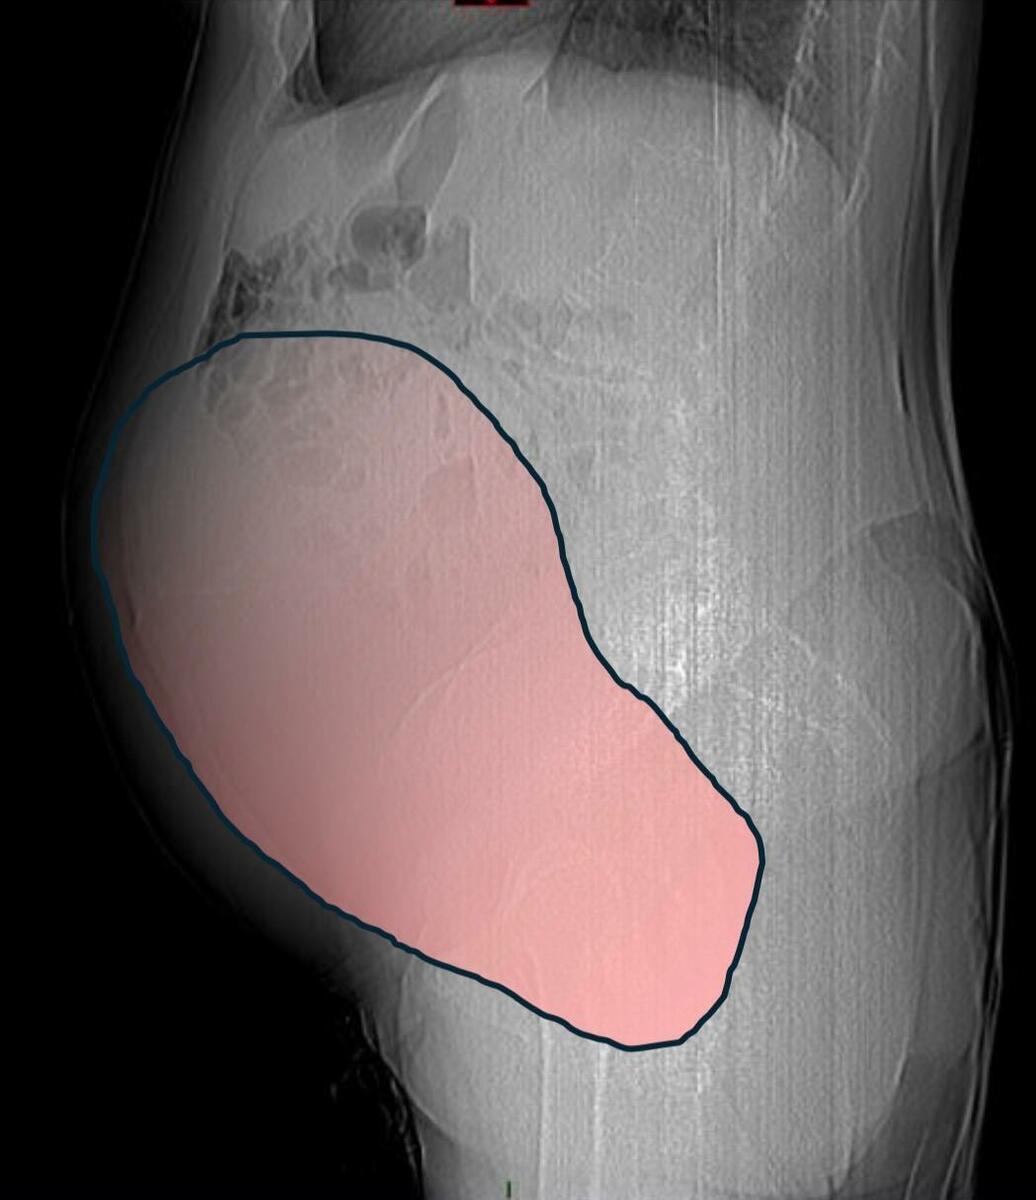

Il caso, definito dai medici un evento “normalmente eccezionale”, è stato preso in carico dalla Chirurgia Ginecologica mininvasiva dell’ospedale Sant’Anna di Torino, diretta dal dottor Paolo Petruzzelli. Nonostante le festività imminenti, la macchina della sanità piemontese si è attivata con una rapidità straordinaria: il 23 dicembre la paziente è stata sottoposta a un intervento durato sei ore che ha visto l’asportazione di una massa di ben 6 chilogrammi e un diametro di 28 centimetri.